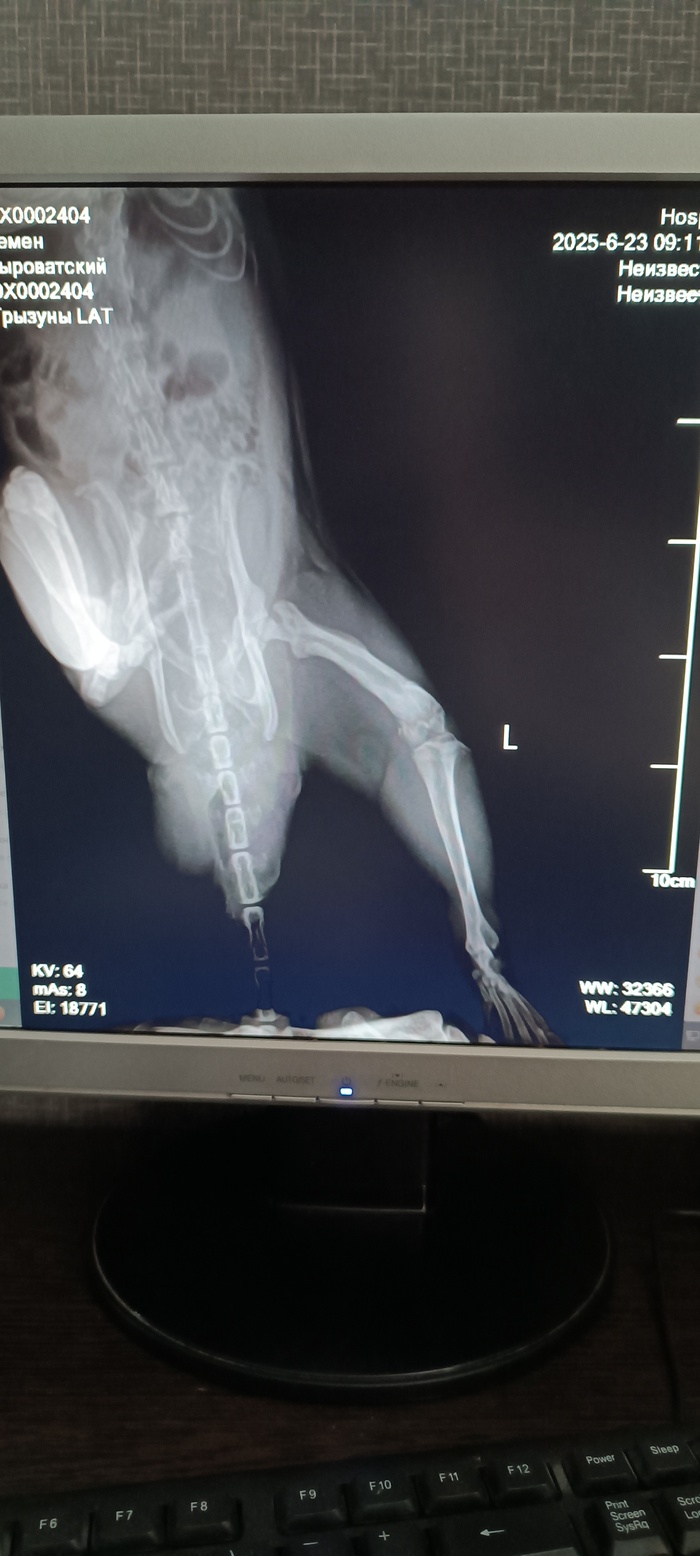

Проблемы с лапой

У Сталина опухла левая задняя лапа. В ночь с 21 на 22 июня. На нее наступать не мог. 23 июня пошли к ратологу. Сделали рентген. Диагноз: повреждение сустава. Отек из-за удара лапы. Сказали ограничить подвижность, прописали вемелкам 0,5мг, давать по 1/3 таблетки дважды в день. Ограничить движение.

Рентген